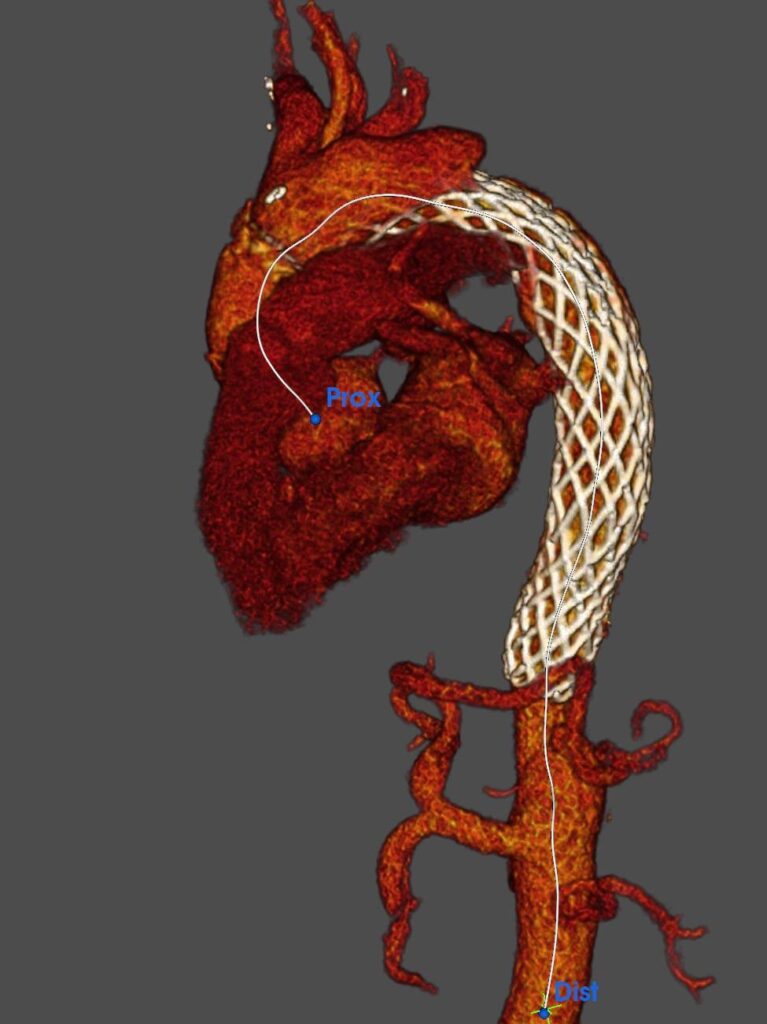

«L’equipe chirurgica ha affrontato l’emergenza con una procedura combinata di altissima complessità, che ha previsto la sostituzione dell’aorta ascendente e lo stenting dell’arco aortico e dell’aorta toracica discendente. La particolarità dell’intervento risiede nell’utilizzo della protesi AMDS (Ascending Stent Graft), un dispositivo di ultima generazione introdotto recentemente nella pratica clinica. A differenza delle tecniche tradizionali, la protesi AMDS è progettata per indurre il rimodellamento dell’aorta. Il dispositivo facilita l’accollamento (la “riattaccatura”) del lembo intimale dissecato, permettendo al sangue di tornare a scorrere correttamente nel lume vero del vaso e riducendo drasticamente il rischio di complicazioni a lungo termine, come la formazione di aneurismi post-dissezione».

«Si è trattato di un intervento estremamente rilevante e complesso – spiega Bruno Chiappini, responsabile della Chirurgia complessa dell’aorta nell’ambito della Cardiochirurgia di Chieti – perché le condizioni del paziente erano disperate. Il cuore dell’intervento è stato l’impianto della protesi AMDS (Ascyrus Medical Dissection Stent), una tecnologia ibrida d’avanguardia progettata specificamente per le dissezioni di tipo DeBakey I. A differenza degli approcci classici, questo dispositivo non si limita a sostituire la porzione danneggiata, ma agisce attivamente sull’intera architettura dell’aorta. Grazie alla sua forza radiale, la protesi ‘stira’ e riattacca i tessuti lacerati, ripristinando immediatamente il corretto afflusso di sangue agli organi periferici e riducendo drasticamente il rischio di complicazioni a lungo termine, come la formazione di aneurismi post-operatori. L’impiego di questa nuova protesi rappresenta un passo avanti fondamentale: non ci limitiamo a gestire l’emergenza acuta, ma favoriamo una vera guarigione anatomica dell’aorta, prevenendo futuri interventi e migliorando radicalmente la prognosi del paziente».